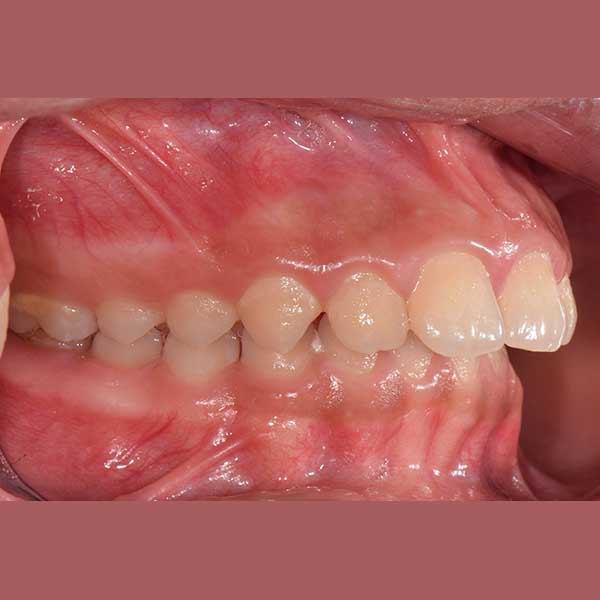

BEFORE

Protruded upper anteriors – fixed metal braces

This little girl has visited me with her mother, she was suffering from the protrusion of her front teeth, which affected her psyche and smile; in addition to its negative impact on her pronunciation

After examining the case, I found that the upper of her front teeth were 8 mm of her lower front teeth, which is a large distance (normal to be 1 to 2 mm). The parents refused the option of tooth extraction, because of her young age, so I solved the problem without extraction because the main problem was caused by the retraction of the lower jaw I fixed it simply with a functional device